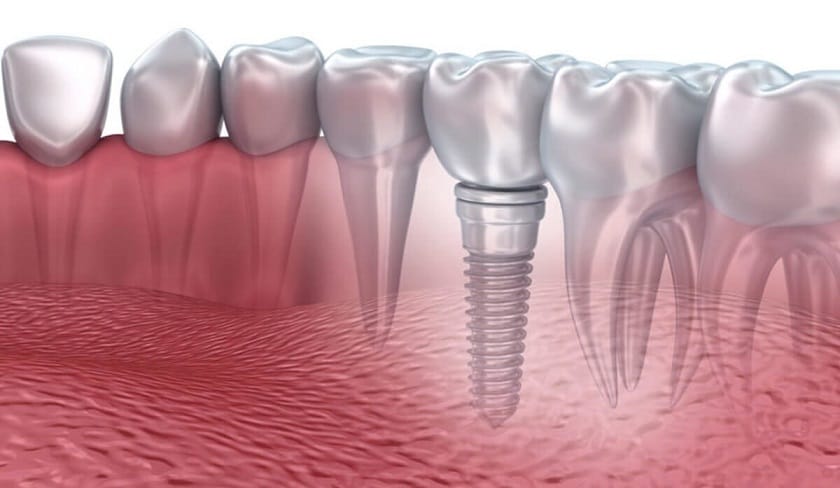

Trong trường hợp này, các bác sĩ thường sẽ tư vấn cho khách hàng sử dụng 2 phương pháp tối ưu hơn là bọc răng sứ và trồng răng implant.